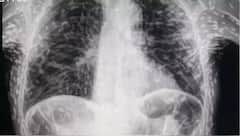

ਖਾਂਘ ਦੇ ਇਲਾਜ ਲਈ ਡਾਕਟਰ ਕੋਲ ਗਿਆ ਵਿਅਕਤੀ, ਹੋਇਆ ਹੈਰਾਨ ਕਰ ਦੇਣ ਵਾਲਾ ਖੁਲਾਸਾ, ਐਕਸਰੇ 'ਚ ਨਜ਼ਰ ਆਏ ਕਈ ਕੀੜੇ